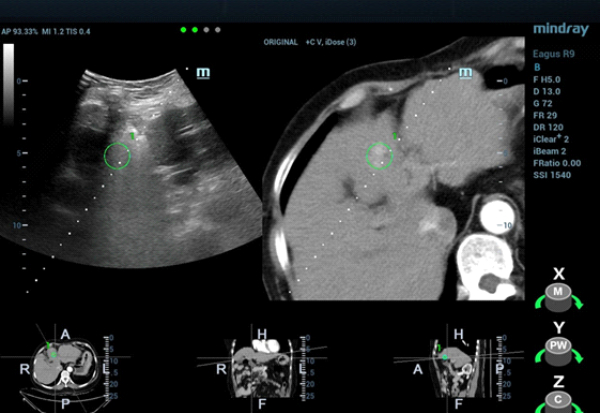

fusion-imaging-fig5

형태 4. 초음파와 CT영상 융합 후 CEUS(Contrast-Enhanced Ultra Sound)를 통해 종괴 위치를 재확인.